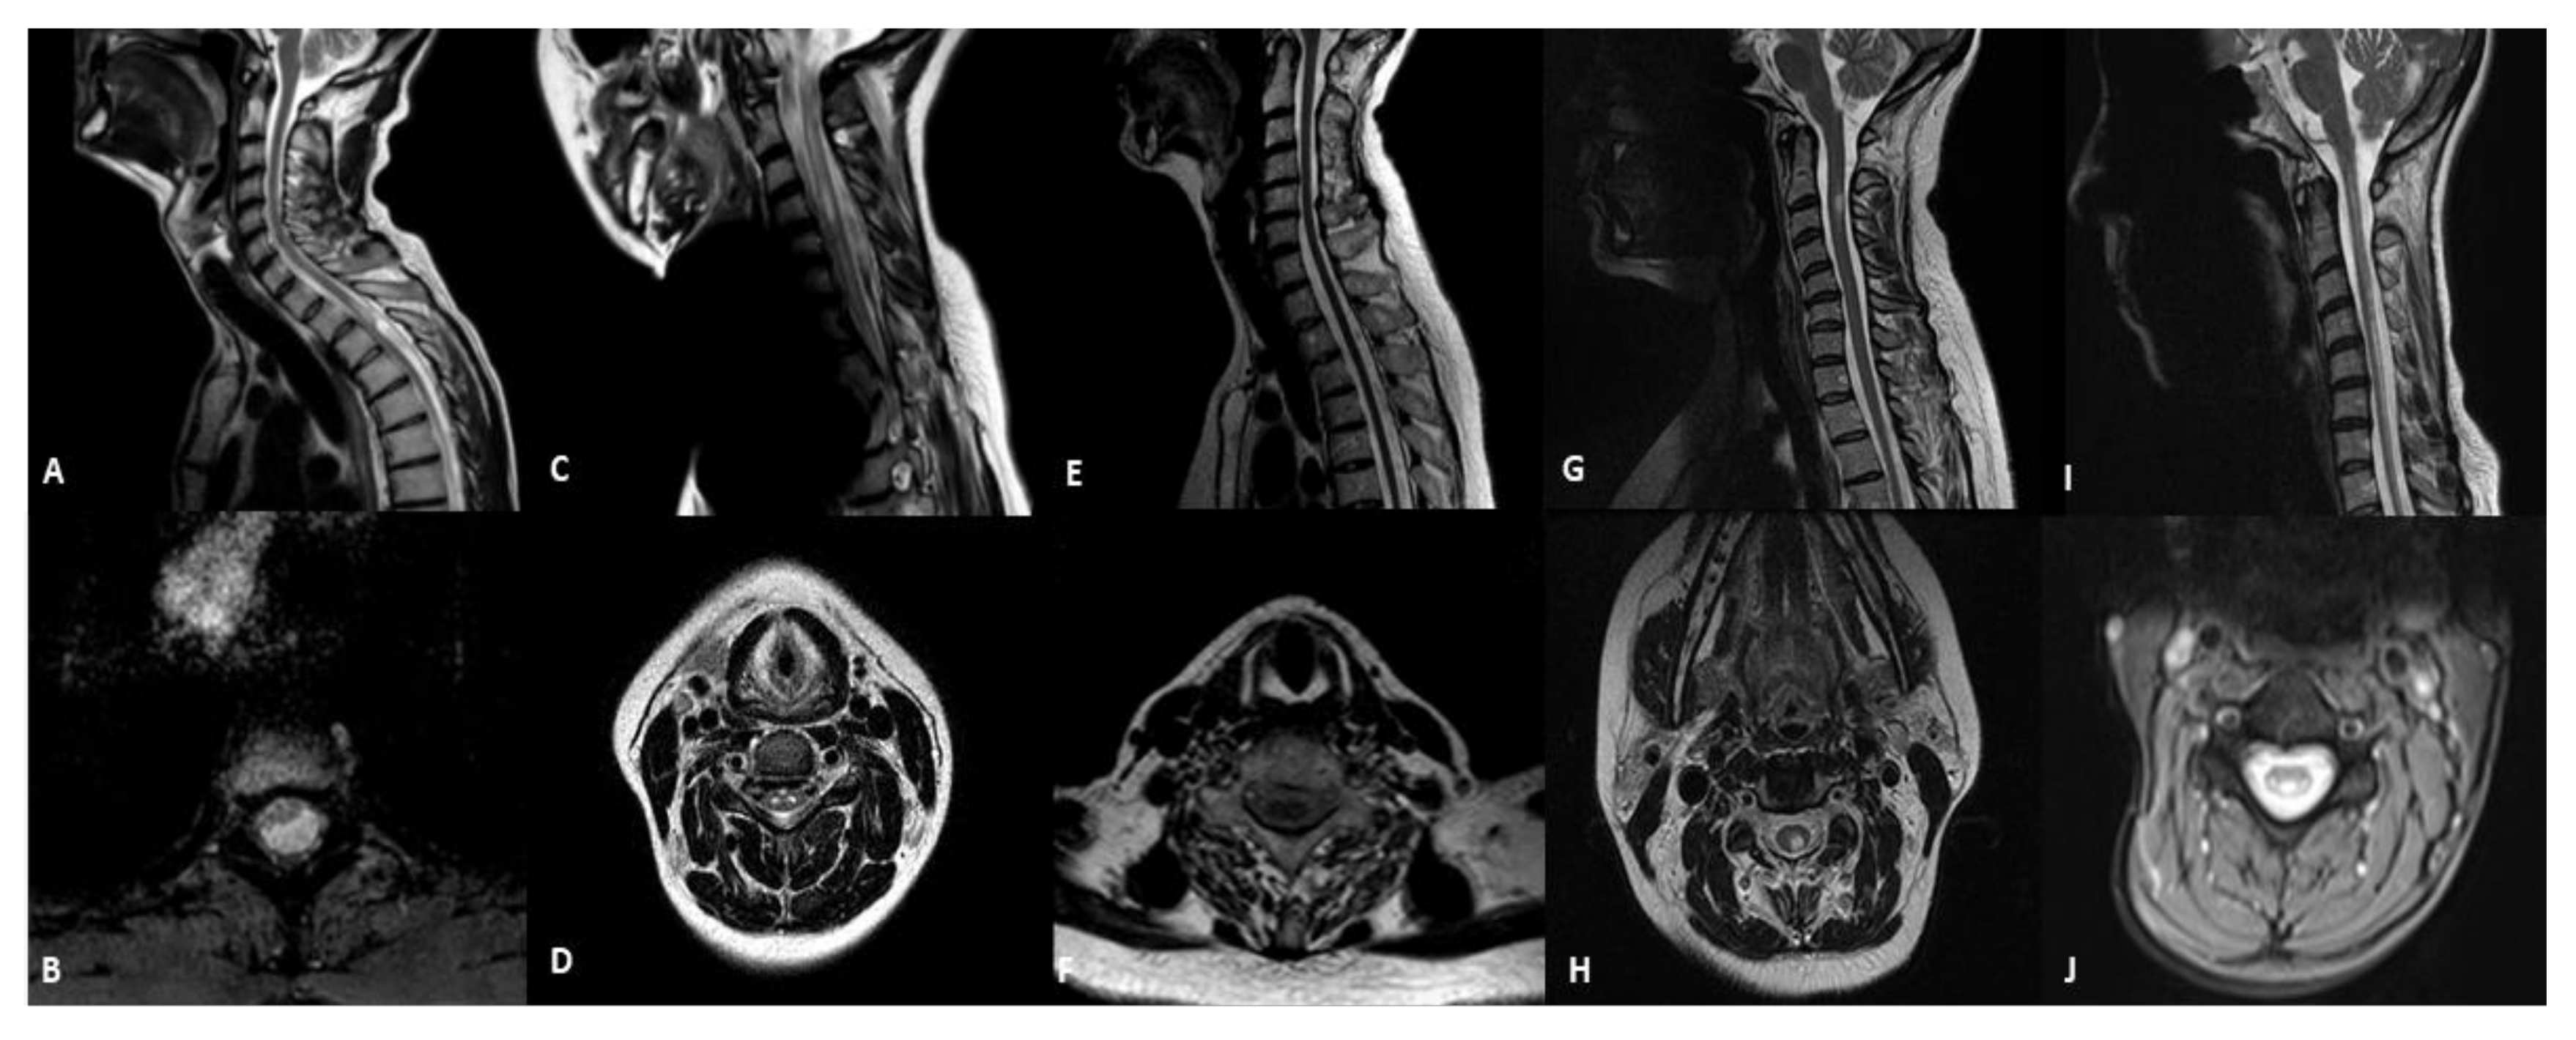

| Patient | Sex | Age at Onset | Age at MRI | Mutations | Phenotype | Spinal Cord Abnormalities |

|---|---|---|---|---|---|---|

| 1 | M | 28 | 45 years | m.3243A > G | MIDD | cystic-like lesion located in the white matter of dorsal and lateral columns |

| 2 | F | 11 | 18 years | m.13513G > A | LS | hyperintensity not involving a selective spinal tract with medullary atrophy |

| 3 | F | 50 | 63 years | POLG | ANS | medullary atrophy without signal alterations |

| 4 | F | 27 | 27 years | m.11778G > A | LHON | selective WMH of dorsalcolumns and lateral columns |

| 5 | F | 8 | 41 years | DARS2 | LBSL | hyperintensity of dorsalcolumns |